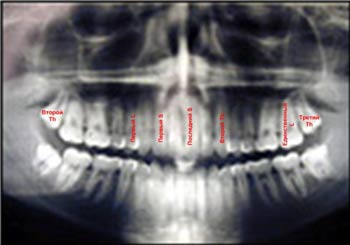

После того, как врач-стоматолог собрал анамнез и провел осмотр пациента, он приступает к рентгенологическому обследованию, с помощью которого оценивает состояние, в котором находится зуб мудрости и десна, его корней, расположенной вокруг корня кости и степень погружения зуба мудрости. После тщательного обследования пациента стоматолог принимает решение о том, необходимо ли удаление зуба мудрости или нет.